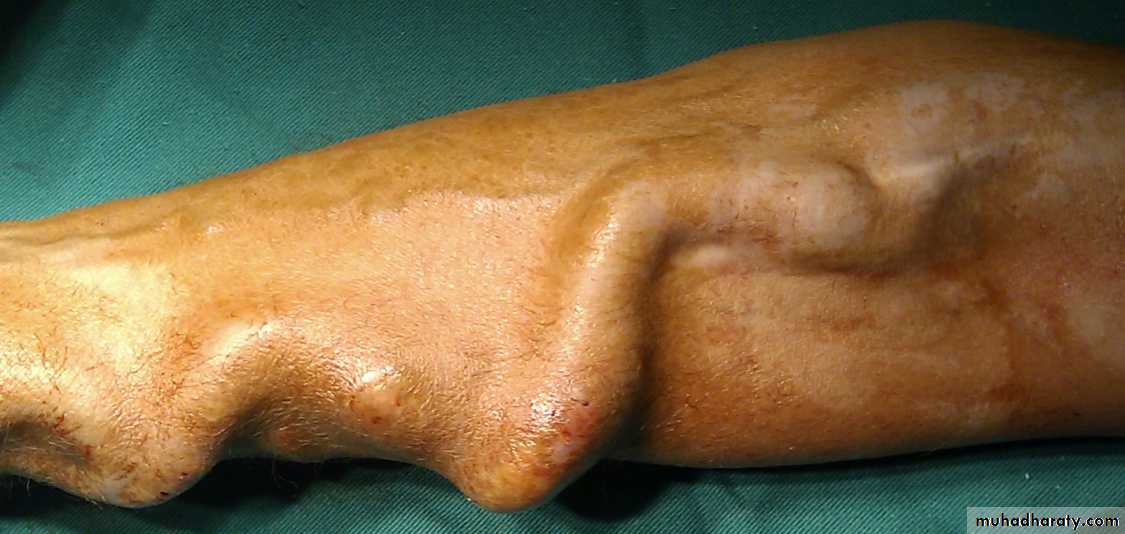

AV fistula (aneurysmal fistula)